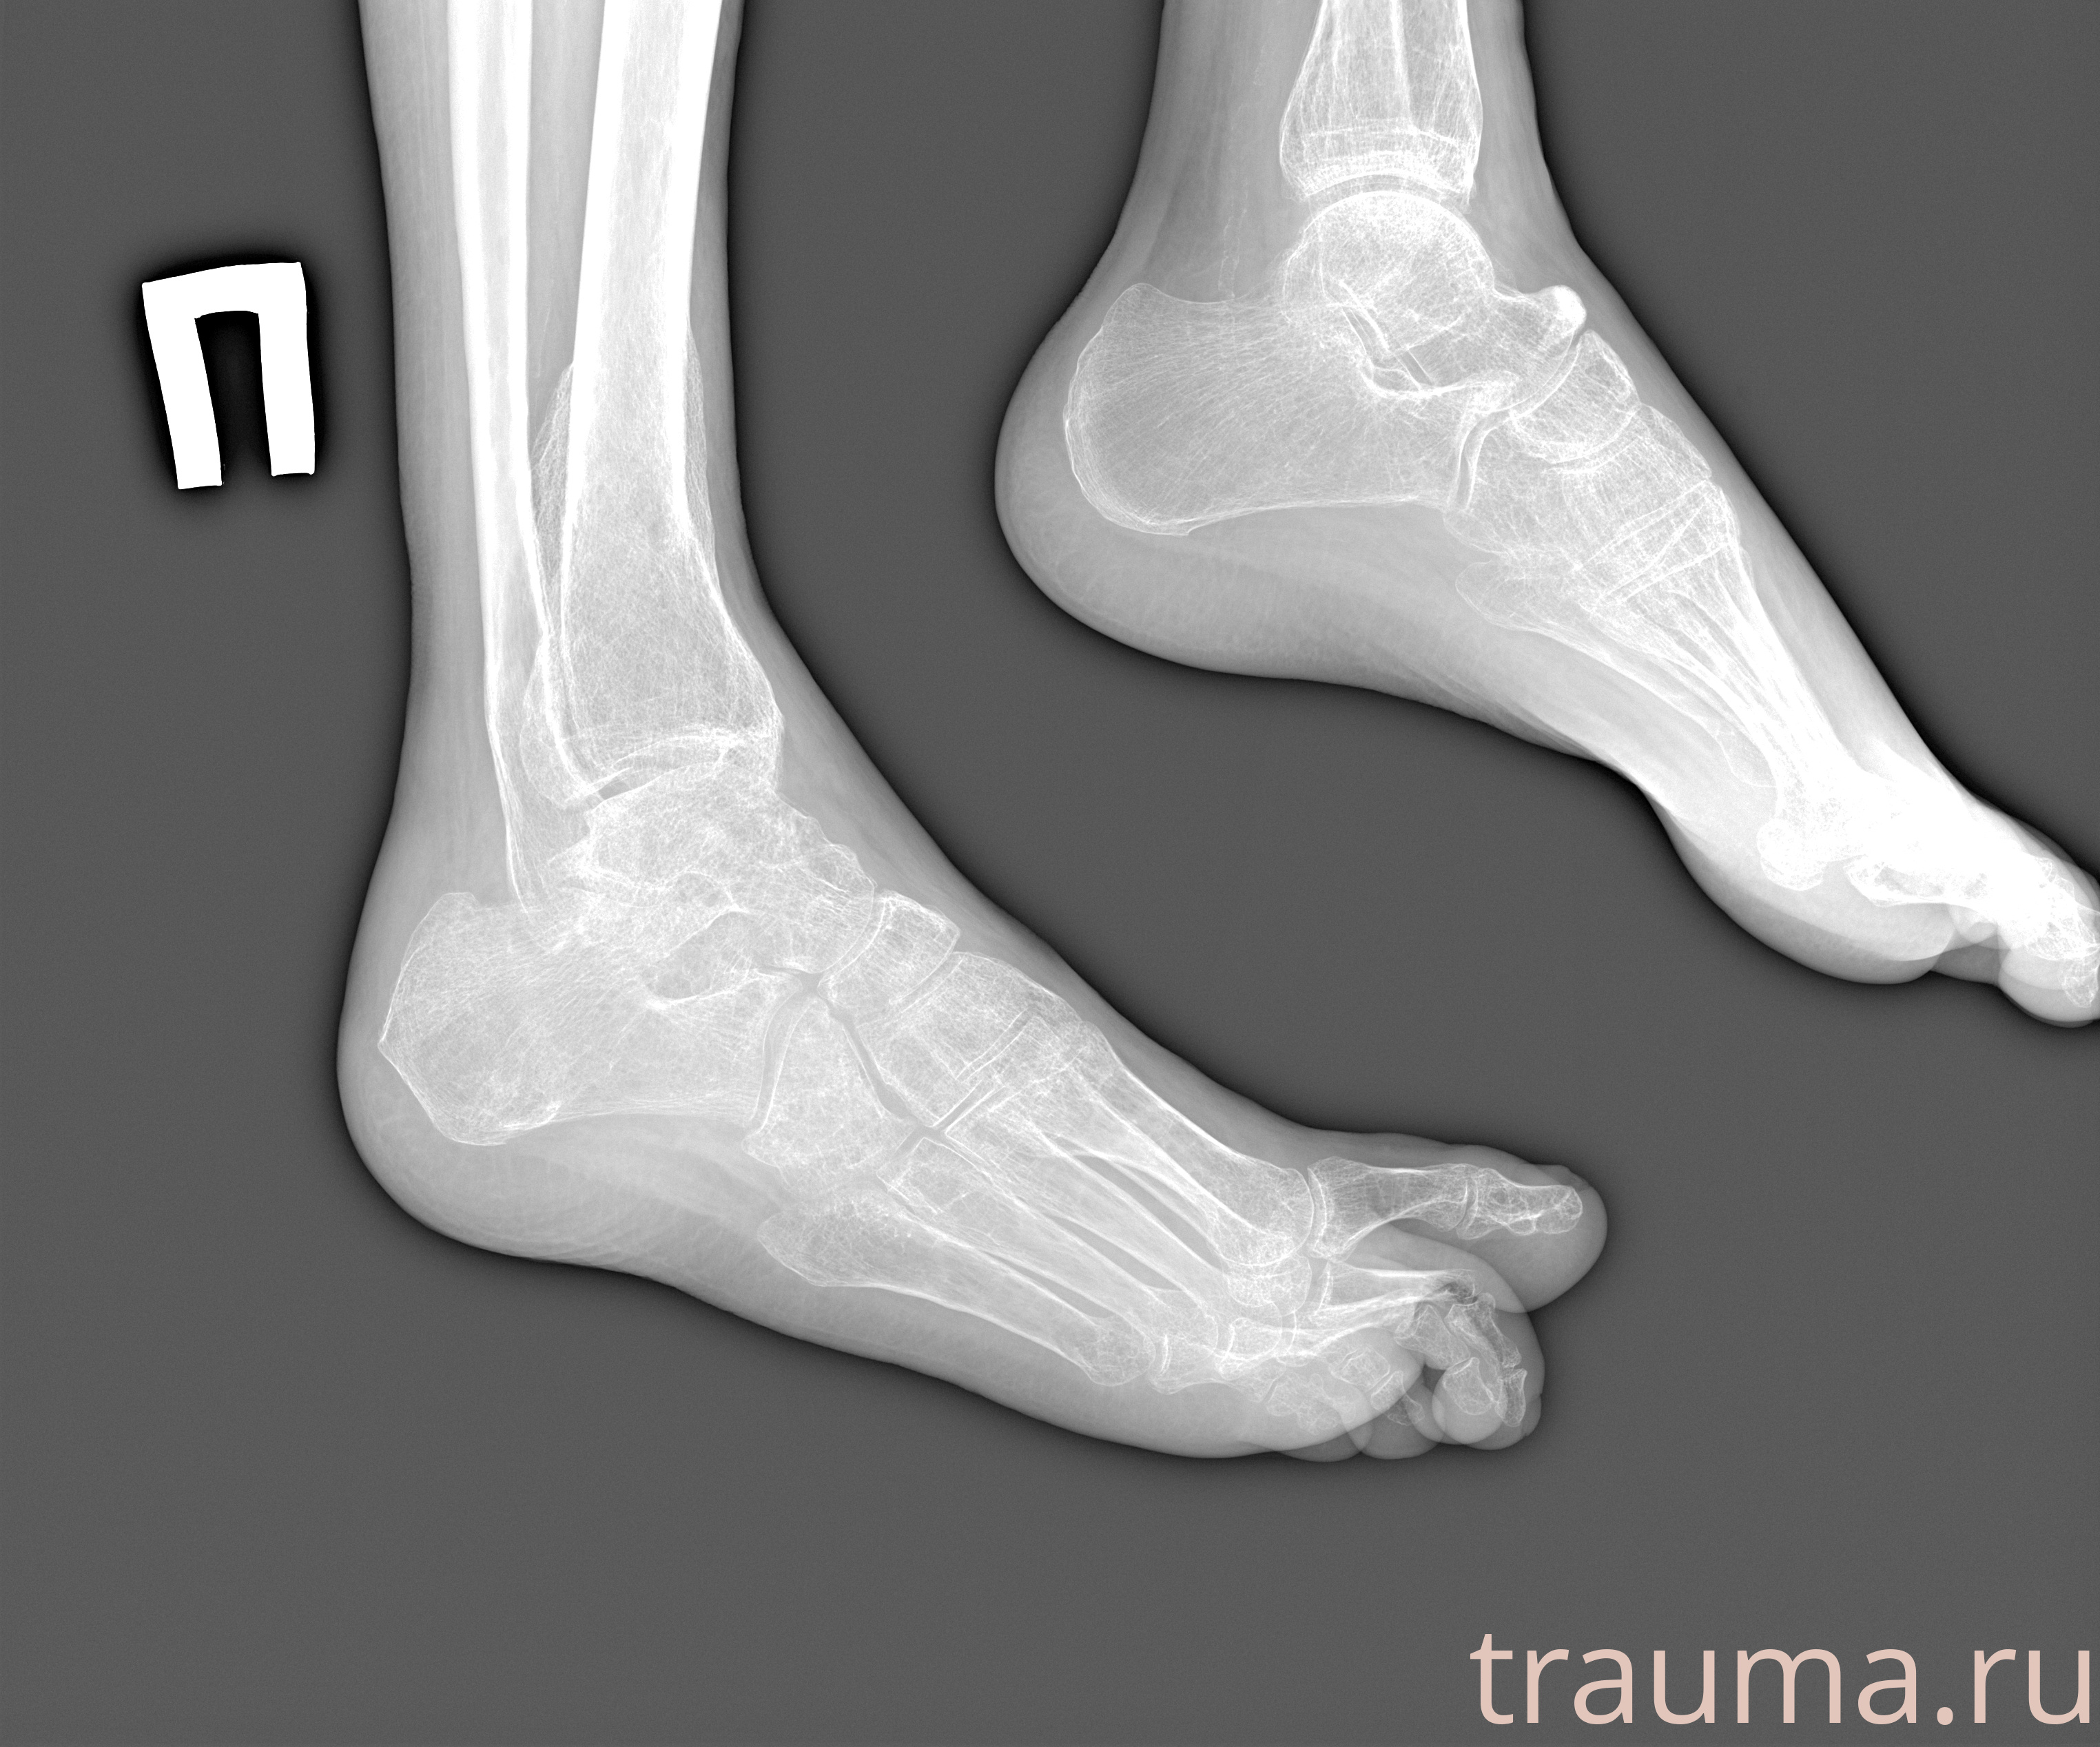

Рентгенограммы

Рентген на дому: по вашему адресу приезжает врач-рентгенолог, травматолог-ортопед с мобильным рентгеновским аппаратом, проводит диагностику травмы или заболевания, делает необходимые рентгенограммы, дает рекомендации по дальнейшему лечению. Получить качественные снимки в домашних условиях возможно благодаря уникальной методике, разработанной МосРентген Центром для института  Склифосовского